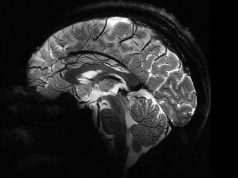

Самый мощный в мире МРТ-аппарат Iseult в несколько раз превзошел конкурентов

Во Франции разработан самый мощный в мире МРТ-аппарат Iseult — он способен обеспечить напряженность поля на уровне 11,7 Тесла. Это в несколько...